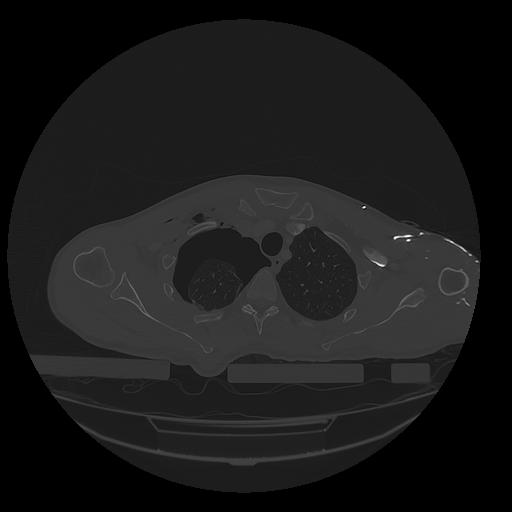

31 PULMON,CE,Vol,1.0,PULMON,,